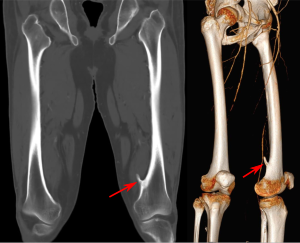

مرض يسبب نمو عظام جديدة فوق العظم

hyperostosis that involves formation of new bone on the surface of preexisting bone

image الإنجليزية

Exostose Femur 54jm- CT cor und VR - 001.svg

١٬٣٠٨ × ١٬٠٥٨؛ ١٨٧ كيلوبايت

[[Tomografia computada]] d'exòstosi diafisària de [[fèmur]] (الكتالانية)